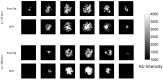

Femoroplasty is a potential preventive treatment for osteoporotic hip fractures. It involves augmenting mechanical properties of the femur by injecting Polymethylmethacrylate (PMMA) bone cement. To reduce the risks involved and maximize the outcome, however, the procedure needs to be carefully planned and executed. An important part of the planning system is predicting infiltration of cement into the porous medium of cancellous bone. We used the method of Smoothed Particle Hydrodynamics (SPH) to model the flow of PMMA inside porous media. We modified the standard formulation of SPH to incorporate the extreme viscosities associated with bone cement. Darcy creeping flow of fluids through isotropic porous media was simulated and the results were compared with those reported in the literature. Further validation involved injecting PMMA cement inside porous foam blocks - osteoporotic cancellous bone surrogates - and simulating the injections using our proposed SPH model. Millimeter accuracy was obtained in comparing the simulated and actual cement shapes. Also, strong correlations were found between the simulated and the experimental data of spreading distance (R(2) = 0.86) and normalized pressure (R(2) = 0.90). Results suggest that the proposed model is suitable for use in an osteoporotic femoral augmentation planning framework.